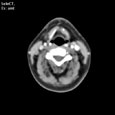

Критический стеноз правой внутренней сонной артерии. Критический стеноз правой внутренней сонной артерии

Пациент U., 69 лет

Критический стеноз правой внутренней сонной артерии.

ЦКБ5 Южной железной дороги, отделение лучевой диагностики.

На КТ-сканах шеи (до уровня основания черепа) в условиях ангиографического режима (в/в ультравист 300 - 100,0 мл 2,5 мл/сек.) определяется окклюзия правой внутренней сонной артерии на 15 мм дистальнее бифуркации общей сонной артерии, дистальнее контрастирование просвета артерии не определяется. Ассиметрично контрастированы яремные вены (справа интенсивность контрастирования значительно ниже).